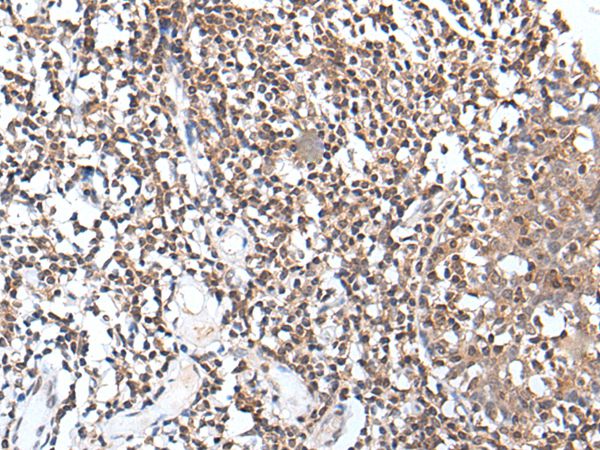

分类: 科研抗体货号: P43469别名: 45170应用: WB,IHC反应种属: Human